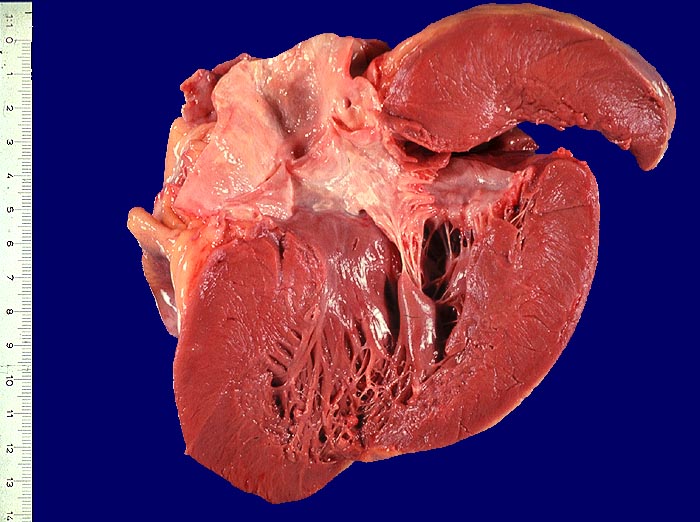

Arterielle Hypertonie: konzentrische Hypertrophie

Herz links

Massive Verdickung der Wand der linken Herzkammer (20mm Dicke gemessen 1cm unterhalb der Mitralklappe.

Normale Dicke des linken Ventrikels 1cm unterhalb Mitralklappe bis 12mm.